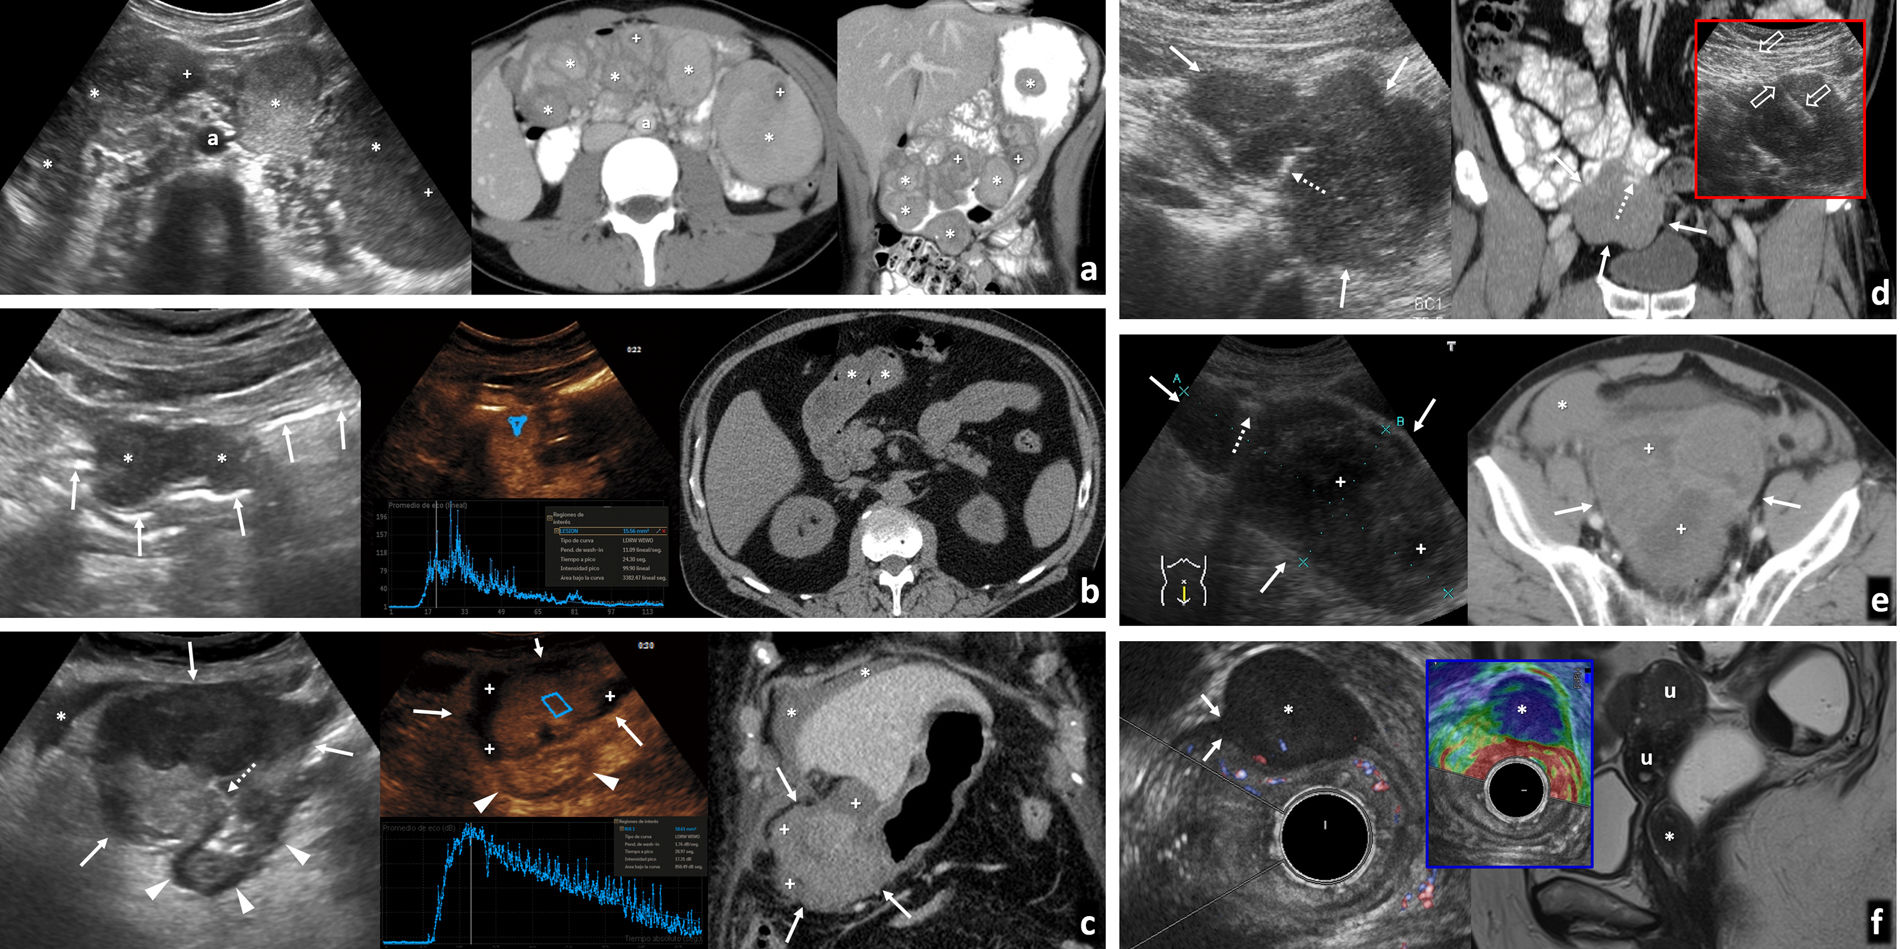

Consecuencia de la ingesta de la larva del parásito en pescado crudo o poco cocinado; aunque los primeros casos se describen en países asiáticos, se ha globalizado. Cuando, como ocurre habitualmente, afecta al estómago, la sintomatología aparece en menos de 24 horas. Provoca intenso dolor agudo en epigastrio, náuseas y vómitos, pudiendo simular patología pancreatobiliar. La ecografía, muchas veces urgente, muestra un importante engrosamiento difuso de la pared gástrica (fig. 1A) y ascitis, planteando diagnóstico diferencial con patología tumoral (linfoma o adenocarcinoma difuso) o gastritis eosinofílica (fig. 1B).

Afectación infecciosa del estómago. A-C) Primer caso de paciente que acude a urgencias por dolor intenso en epigastrio, con náuseas y vómitos abundantes de pocas horas de evolución, por el que se solicita ecografía urgente (A). Engrosamiento circunferencial y simétrico (flechas finas) de la pared de cuerpo y antro gástrico, que se correlaciona con las imágenes de tomografía computarizada (TC) en incidencia axial (B) y reconstrucción coronal (C) que se realizó a continuación, donde predomina un engrosamiento hipodenso (*) que orienta a edema submucoso. Con la sospecha de cuadro inflamatorio sin poder descartar otras causas, el paciente es sometido a endoscopia que muestra engrosamiento de pliegues gástricos y eritema mucoso con el resultado histológico en la biopsia de gastritis crónica superficial con eosinofilia, muy sugerente de gastritis por anisakis, aunque no pudo identificarse el parásito. El cuadro se resolvió en pocos días con tratamiento sintomático. D y E) Segundo caso de paciente que refiere dolor epigástrico de semanas de evolución con vómitos ocasionales. Se solicita ecografía como prueba de estudio inicial, que muestra un engrosamiento de la pared del antro gástrico, asimétrico, más marcado en la pared anterior (flecha gruesa), sospechoso de origen tumoral (D). La TC realizada posteriormente (E) presenta un hallazgo similar, mostrando una captación irregular de contraste (cabezas de flecha) de la mucosa gástrica, con una adenopatía prominente por delante de la vena cava inferior (+) sospechosa de diseminación ganglionar. La endoscopia y biopsia posterior confirman el diagnóstico de adenocarcinoma.

Intestino delgado distalLas infecciones del íleon terminal con frecuencia pueden extenderse al ciego (fig. 2). El principal diagnóstico diferencial es la enfermedad inflamatoria intestinal, en etapas precoces habitualmente indistinguible (tabla 2).

Afectación infecciosa del íleon distal. Primer caso de paciente joven con dolor abdominal y diarrea que consulta en el servicio de urgencias. Se realiza ecografía para filiar el origen del cuadro. Presentamos imágenes en corte longitudinal (A y B) del íleon terminal, objetivando un engrosamiento de la pared que conserva la estratificación de sus capas, afectando a la capa mucosa (cabezas de flecha) y submucosa (*) y respetando la capa muscular (flechas finas), característico de las enteritis infecciosas frente a otras causas de afectación intestinal. El estudio mediante Doppler color muestra un aumento de la vascularización secundaria al cuadro infeccioso (C). Se acompaña de tumefacción e hiperecogenicidad de la grasa mesentérica adyacente (+) y un ganglio ileocólico aumentado de tamaño de naturaleza reactiva (flecha gruesa). El cultivo de heces resultó positivo para Yersinia enterocolitica. Tras tratamiento antibiótico y sintomático, la paciente mejoró progresivamente hasta al alta. Segundo caso de paciente de 18 años, que acude al servicio de urgencias por febrícula y dolor abdominal en fosa iliaca derecha de horas de evolución. En la valoración inicial se realiza ecografía con la sospecha de apendicitis aguda, en la que se aprecia un engrosamiento de la pared de íleon terminal que se extiende al ciego (D) y un apéndice ileocecal de calibre normal (E), que orienta a cuadro infeccioso, descartando la sospecha diagnóstica que motivó la petición. A las 24 horas, se solicita una tomografía computarizada abdominal. Mostramos una imagen de reconstrucción coronal del estudio en la zona de interés (F), que muestra los mismos hallazgos. Dada la persistencia de la clínica, se decide intervenir quirúrgicamente a la paciente, practicando una resección ileocólica con el resultado histológico de enterocolitis supurada con apéndice normal. No pudo determinarse en el estudio microbiológico el agente infeccioso que originó el cuadro.

Afectación infecciosa del peritoneo. A-D) Hallazgos característicos de peritonitis tuberculosa en varios pacientes. Adenopatías mesentéricas (A) con centro hipoecoico por presencia de necrosis (*), afectación esplénica (B) con absceso en polo inferior del bazo (cabeza de flecha) y ascitis (C) con punteado ecogénico por material denso. Un dato significativo es el engrosamiento del epiplón mayor (flechas gruesas), que se aprecia con detalle en la ecografía (D), y se correlaciona con la imagen tomográfica mostrada en la esquina inferior izquierda. Plantea el diagnóstico diferencial con infiltración tumoral, por lo que precisa habitualmente de estudio histológico tras la obtención de una muestra que puede ser guiada ecográficamente como se aprecia en la imagen de la esquina inferior derecha. E-G) Peritonitis de otro origen. En el primer caso (E), paciente con cuadro de apendicitis aguda que se acompaña de discreta cantidad de líquido libre entre asas, con punteado ecogénico (+) y engrosamiento lineal del peritoneo parietal (flecha fina) que indica la presencia de peritonitis focal asociada. El segundo caso, peritonitis parasitaria en paciente con quiste hidatídico hepático (F) con membranas plegadas y presencia de líquido perihepático (G) que indica complicación del mismo con rotura y diseminación peritoneal del contenido.

PeritoneoLa peritonitis tuberculosa es la manifestación más frecuente de la tuberculosis abdominal. Clásicamente se describen tres patrones: peritonitis húmeda, la más frecuente (90%), con ascitis de distribución libre o loculada, punteado ecogénico por alta densidad del líquido y engrosamiento peritoneal (fig. 3C); peritonitis seca, con escasa cantidad de líquido y adherencias completas o incompletas; y peritonitis fibrótica, con nódulos y masas mesentéricos y engrosamiento nodular del omento. La ecografía permite explorarlos con detalle y sirve de guía para la biopsia diagnóstica (fig. 3D). Descrita como la gran imitadora, su diagnóstico diferencial incluye la carcinomatosis peritoneal, el linfoma, la enfermedad de Crohn, el mesotelioma, el pseudomixoma peritoneal o la peritonitis piógena.

La peritonitis piógena (fig. 3E) es el resultado de la complicación de una infección abdominal generalmente de origen intestinal y puede derivar en abscesos, que a menudo requieren drenaje percutáneo guiado por ecografía. La peritonitis bacteriana espontánea es una complicación de cirrosis descompensada, a sospechar en caso de ascitis con fiebre o deterioro clínico. Su diagnóstico precisa paracentesis diagnóstica ecoguiada. Cabe mencionar las peritonitis parasitarias, que en nuestro medio suelen deberse a la rotura de un quiste hidatídico hepático (fig. 3F y G)32,33.

Pólipos y carcinomas. A) Pólipo adenomatoso hipoecogénico de 13 mm (flechas) en la luz del colon transverso, con un pedículo que sigue la estructura en capas de la pared (cabezas de flecha) y flujo demostrado en Doppler (derecha). Hallazgo incidental en varón de 77 años. B) Pólipo adenomatoso hipoecogénico (flechas) en el colon sigmoide, hallazgo incidental en varón de 44 años. La estabilidad de la imagen en el tiempo y la rigidez tisular, con tonos azules en la imagen de elastografía cualitativa de presión o strain (derecha), confirman el hallazgo. C) Carcinoma Hagitt 1 sobre pólipo adenomatoso hipoecogénico de 15 mm (flecha) en la luz del colon izquierdo distal, con un vaso en su interior en Doppler y una pequeña ulceración superficial (flecha hueca). Hallazgo incidental en ecografía por ateromatosis en varón de 67 años. En el recuadro, imagen de colonoscopia previa a resección. D) Carcinoma Hagitt 1 sobre pólipo adenomatoso hipoecogénico de 20 mm (flecha) en la luz del colon sigmoide, con un vaso en su pedículo en Doppler (cabeza de flecha). Hallazgo incidental en estudio por molestias abdominales inespecíficas en mujer de 78 años. En el recuadro, imagen durante la resección endoscópica. E) Adenocarcinoma infiltrante de colon sigmoide T2 N0 M0 en ecografía por anemia en varón pluripatológico de 85 años. Engrosamiento hipoecogénico infiltrante con retracción de la pared posterior del colon (flechas), sin rebasar la capa muscular propia hipoecogénica (cabezas de flecha). La ecografía es más precisa que la tomografía computarizada (TC) (no mostrada) en la estadificación locorregional en este caso, permitiendo un abordaje quirúrgico laparoscópico rápido y limitado en un paciente clínicamente complejo. F) Carcinoma polipoideo en recto inferior, hallazgo ecográfico empleando la vejiga (v) como ventana acústica. Lesión nodular hipoecogénica (flechas) de 33 mm. En el recuadro, curva intensidad/tiempo de ecografía con contraste para confirmar el hallazgo (vídeo 1). p: próstata. Imagen inferior: correlación en resonancia magnética (RM) sagital potenciada en T2 con gel endorrectal para estadificación locorregional. G) Carcinoma de transición colorrectal como masa exofítica ulcerada y necrótica que simula GIST. imagen superior: ecografía, sección transversal (izquierda) y longitudinal (derecha) sobre hipogastrio. Masa hipoecogénica heterogénea (flechas) por necrosis, con focos de gas (flechas huecas) por ulceración. Imagen inferior: TC sagital. La masa contacta con la cara anterior del recto-sigma (r). Se sospechó GIST, pero correspondió a un adenocarcinoma con un patrón infrecuente de presentación. H) Adenocarcinoma gástrico T4a N2 M0. Imagen superior: ecografía por síndrome constitucional en varón de 83 años. Engrosamiento hipoecogénico marcado e irregular de la pared del estómago (e: luz gástrica), con ulceraciones (no mostrado) y clara extensión nodular a la grasa del ligamento gastrocólico (cabezas de flecha). La elastografía (recuadro inferior izquierdo) muestra marcada rigidez tisular. Se ven también adenopatías regionales (flecha hueca en recuadro inferior derecho). Imagen inferior: TC coronal en fase portal. La gran delgadez del paciente hace que la estadificación sea menos precisa que con ecografía. I) Adenocarcinoma rectal T1 sobre pólipo velloso (flechas) en varón de 67 años. La ecografía endorrectal (izquierda) muestra una lesión polipoidea de ecogenicidad intermedia, definiendo con más precisión que la RM (derecha: T2 transversal con gel endorrectal) la indemnidad de la capa muscular propia (hipoecogénica), permitiendo la resección transanal. J) Adenocarcinoma de recto inferior T3a superficial en varón de 72 años. La ecografía endorrectal (izquierda) muestra con precisión un engrosamiento hipoecogénico excéntrico en la cara anterior del recto inferior, que transgrede la capa muscular propia hipoecogénica con nodulaciones superficiales (flechas), confirmando extensión T3 superficial. Se demuestra la preservación de un plano graso (cabezas de flecha) con la próstata (p). La RM transversal T2 (derecha) plantea dudas en este caso desde T2 hasta T4b por infiltración prostática. K) Mucocele apendicular. Imagen superior: hallazgo ecográfico incidental en mujer de 77 años con colecistitis aguda litiásica. Masa ovoidea con estructura interna en capas con ecogenicidades alternantes (patrón “en capas de cebolla” característico) en fosa iliaca derecha (flechas). Imagen inferior: la TC axial muestra finas calcificaciones parietales, pero no es capaz de demostrar la estructura mucinosa de la lesión quística con la precisión de la ecografía. L) Mucocele apendicular sobreinfectado y comunicado con el ciego. Imagen superior: ecografía en varón de 62 años con dolor abdominal y fiebre. Masa quística heterogénea en fosa iliaca derecha (flecha), con focos ecogénicos que representan gas (cabeza de flecha) y calcificaciones parietales (flecha hueca). Imagen inferior: la TC demuestra además la comunicación del mucocele con la luz del ciego (flecha discontinua).

Tumores neuroendocrinos. A) Tumor carcinoide de íleon terminal. Mujer de 62 años con vómitos y dolor abdominal. Antecedente de macroadenoma hipofisario intervenido. Imagen superior: ecografía. Imagen inferior: tomografía computarizada (TC) coronal. Lesión nodular hipoecogénica con abundante vascularización en Doppler y TC (flechas), en el ángulo interno de tramo plegado de íleon distal (+), con peristaltismo ineficaz a tiempo real (vídeo 2). Además, adenopatías hipoecogénicas y vascularizadas (cabezas de flecha) en meso regional tumefacto y ecogénico (m). Se diagnostica MEN-1. En el recuadro: implante endometriósico (*) en íleon terminal (+) en otra paciente, como nódulo hipoecogénico que infiltra la serosa, retrayendo el asa y respetando las capas profundas, que muestra hallazgos similares y con el que hay que establecer diagnóstico diferencial (no vascularizado y sin afectación adenopática en este caso). B) Carcinoide ileal solo manifestado como masa mesentérica. Imagen superior: biopsia percutánea (flechas huecas) guiada ecográficamente de nódulo mesentérico hipoecogénico (flecha), que demostró metástasis ganglionar de tumor neuroendocrino. Imagen inferior: TC coronal con contraste oral e intravenoso. Nódulos adenopáticos mesentéricos (flechas). En la cirugía se identificó un carcinoide milimétrico intestinal primario y retrospectivamente podría corresponder al pequeño defecto de repleción indicado por la cabeza de flecha. C) Carcinoides yeyunales múltiples y metástasis ganglionares mesentéricas. Mujer de 71 años con molestias abdominales inespecíficas. Imágenes superiores: ecografías. Centrales e inferiores: imágenes axiales de entero-TC en dos planos diferentes. Se detectan hasta 5 tumores hipoecogénicos e hipervasculares (uno no mostrado) en tramos plegados de yeyuno (flechas), con un pequeño conglomerado adenopático también hipervascular e hipoecogénico en el meso tributario (cabezas de flecha). D) Síndrome de Zollinger-Ellison por tumor neuroendocrino de tipo II (gastrinoma) de tracto digestivo superior. Varón de 44 años con vómitos, diarrea y shock. Imagen izquierda: ecografía. Imagen derecha superior: TC axial. Abundante líquido en estómago (e), duodeno (d) y yeyuno proximal (no mostrado), con marcado engrosamiento de pliegues gástricos (cabezas de flecha). Medial al duodeno y posterior al páncreas se ve un nódulo hipervascular y levemente ecogénico (flechas) en el seno de una estructura ganglionar. Esta región está dentro del llamado “triángulo del gastrinoma”. Derecha centro: gammagrafía con octeótrida. Se confirma captación por parte del nódulo (flecha). También hay hipergastrininemia. Derecha inferior: pieza quirúrgica del gastrinoma (flechas) en el seno de un ganglio. E) Carcinoma neuroendocrino gástrico de tipo III. Varón de 59 años con síndrome constitucional. La ecografía muestra abundantes metástasis hepáticas (m) y, empleando el bazo (b) como ventana acústica, un tumor infiltrante en la curvatura mayor del estómago. Se sospechó un adenocarcinoma, pero la biopsia endoscópica demostró un carcinoma neuroendocrino. F) Tumor neuroendocrino rectal. Hallazgo en la colonoscopia por test de sangre oculta en heces positivo en varón de 62 años. Imagen superior: ecografía transrectal. Imagen inferior: RM T2 axial. Tumor de 7× 5 mm (flechas) con comportamiento hipoecogénico e hipointenso en T2, situado en la parte profunda de la capa submucosa del recto inferior, con moderada rigidez tisular en elastografía (recuadro central), con strain ratio de 10 con respecto a la pared rectal normal. Se realizó una resección endoscópica transanal.

Tumores hematológicos (fig. 7)Aunque infrecuentes (1-8%), el tracto gastrointestinal supone el asiento extraganglionar más habitual del linfoma, casi siempre no Hodgkin-B, primario o secundario. El orden de frecuencia de afectación es estómago, intestino delgado (especialmente íleon distal), colon-recto y esófago. Ecográficamente suele presentarse como masa o, más habitualmente, un engrosamiento mural circunferencial hipoecogénico marcado, más homogéneo, largo y menos obstructivo que el carcinoma, en ocasiones preservando relativamente la estructura en capas. Puede ser multifocal, ulcerarse, cavitar y, por destrucción del plexo mioentérico, producir dilatación aneurismática de la luz. Suele acompañarse de adenopatías hipoecogénicas prominentes, y a veces de afectación peritoneal o de otros órganos. Con contraste muestra realce homogéneo, más discreto y tardío que otros tumores36,59,60.

Linfomas gastrointestinales. A) Linfoma difuso de células grandes de íleon terminal. Mujer de 36 años. Imagen izquierda: tomografía computarizada (TC) coronal con contraste oral e intravenoso. Imagen derecha: ecografía. Engrosamiento mural hipoecogénico e hipovascular marcado en un tramo largo de íleon distal (flechas) cuya luz se encuentra dilatada (*). Se acompaña de una masa mesentérica adyacente de ecogenicidad similar (cabezas de flecha), sobre la que se realizó BAG guiada ecográficamente (flechas huecas). B) Linfoma difuso de células grandes de yeyuno distal. Varón de 70 años. Imagen superior: TC coronal con contraste oral e intravenoso. Imagen inferior: ecografía. Engrosamiento mural hipoecogénico e hipovascular marcado en un tramo más corto de yeyuno distal (flechas), también con dilatación aneurismática (*) y una masa mesentérica adenopática acompañante (cabeza de flecha). El diagnóstico se consiguió con la biopsia percutánea del engrosamiento intestinal (no mostrado). C) Enfermedad inmunoproliferativa de intestino delgado (o “linfoma mediterráneo”, subtipo de linfoma extranodal de la zona marginal). Varón de 17 años con diarrea, fiebre y dolor abdominal. La ecografía muestra adenopatías mesentéricas homogéneas (cabezas de flecha), engrosamiento de pliegues de yeyuno proximal (flechas), con una invaginación larga de yeyuno (flechas discontinuas) con mesenterio en su interior (m), así como pequeñas lesiones focales hepáticas hipoecogénicas (flechas huecas). El diagnóstico se obtuvo con la biopsia de dos lesiones focales hepáticas (no mostrado). D) Linfoma T gástrico de alto grado asociado a enteropatía. Varón de 61 años con diagnóstico de enfermedad celiaca. Imagen superior: TC. Imagen inferior: BAG guiada ecográficamente. Engrosamiento circunferencial hipovascular e hipoecogénico (no mostrado) de antro gástrico (flechas), con múltiples lesiones focales hepáticas hipocaptantes (cabezas de flecha) y levemente hipoecogénicas. En la gastroscopia se ve una lesión antral ulcerada, pero las biopsias son repetidamente negativas. El diagnóstico se consigue con la biopsia percutánea de las lesiones hepáticas. E) Linfoma folicular de bajo grado de yeyuno proximal. Varón de 73 años. Imagen izquierda: TC axial (superior) y coronal MIP fino (inferior). Imagen derecha: ecografía, corte transversal (superior) y biopsia percutánea. Engrosamiento mural excéntrico de un tramo de yeyuno proximal (cabezas de flecha) con una gran masa mesentérica (flechas) que se extiende hasta el ángulo de Treitz (t), con escaso efecto de masa sobre los vasos mesentéricos a su través. a: aorta. Ecográficamente se define mejor la heterogeneidad de este conglomerado adenopático, lo que permite dirigir la biopsia percutánea a la parte más sólida de la masa mesentérica (flechas huecas). Persiste en remisión completa tras 3 años de iniciar la quimioterapia. F) Linfoma de Burkitt ileocecal. Mujer de 46 años. Imagen izquierda: ecografía. Imagen derecha: TC coronal. Engrosamiento mural importante, excéntrico, en la región ileocecal (flechas) sin estenosis de la luz (*) y con cierta sensación de preservación de la estructura ecográfica en capas a pesar de la magnitud del engrosamiento. Se acompaña de un conglomerado adenopático mesentérico (cabezas de flecha) que se define con más precisión en la ecografía, así como numerosas lesiones focales hepáticas (flechas discontinuas) y ascitis (+). Persiste en remisión completa tras 4 años de iniciar la quimioterapia. G) Linfoma de células del manto de alto grado con afectación de ángulo esplénico del colon. Mujer de 69 años. Imagen izquierda: TC coronal. Imagen derecha: ecografía. Gran masa que engloba el ángulo esplénico del colon (c) y se extiende hacia su meso (flechas). Se acompaña de afectación de íleon distal (i), vesícula (v) y útero (u) como engrosamiento visceral, así como adenopatías mesentéricas (cabezas de flecha), ascitis (+) y linfomatosis peritoneal (flechas discontinuas). El diagnóstico se obtuvo con biopsia percutánea ecodirigida de la masa del mesocolon (flechas huecas).

GIST gastrointestinales. A) Múltiples GIST gástricos en el contexto de síndrome de Carney-Stratakis. Se sumaban varios paragangliomas cervicales (no mostrado). Mujer de 20 años. De izquierda a derecha: ecografía (corte transversal en epigastrio), tomografía computarizada (TC) axial con contraste oral e intravenoso en el mismo plano y TC coronal. Hay innumerables nódulos y masas sólidos (*) de ecogenicidades diversas, dependientes de la pared gástrica. En algunos se aprecian focos de degeneración quística o necrótica (+). a: aorta. No hubo respuesta a imatinib y requirió gastrectomía subtotal. No había mutación en c-KIT ni PDGFRA y sí mutación germinal en una subunidad de SDH (habitual en estos casos). Los GIST en síndromes afectan más a mujeres jóvenes y niñas, con subtipo histológico más frecuentemente epitelioide que fusocelular. Frecuentemente aparecen como múltiples tumores gástricos, con adenopatías menos excepcionales y más rara respuesta a imatinib que los esporádicos. B) GIST gástrico pequeño con crecimiento endofítico. Varón de 71 años. De izquierda a derecha: ecografía (corte transversal en epigastrio), ecografía con contraste y TC axial sin contraste (antecedente de reacción adversa grave). Hallazgo ecográfico incidental de tumor lobulado homogéneamente hipoecogénico (*) con crecimiento endofítico en el antro gástrico. Pese a ser un estudio con sonda convexa de baja frecuencia en paciente obeso, se puede apreciar cómo la lesión depende de la capa muscular propia, encontrándose inmediatamente superficial a la capa submucosa ecogénica más proximal. Las flechas señalan a la luz gástrica. En ecografía con contraste la lesión realza de forma rápida y homogénea, con lavado posterior. Ciertos equipos y PACS permiten un análisis cuantitativo. En TC sin contraste la lesión pasa prácticamente desapercibida. C) GIST gástrico con crecimiento exofítico y complicación hemorrágica espontánea. Mujer de 82 años. Dolor abdominal y anemización. De izquierda a derecha: ecografía (corte transversal en hipocondrio derecho), ecografía con contraste y TC coronal con contraste. Masa heterogénea (flechas) con crecimiento exofítico desde el antro gástrico (cabezas de flecha) y una ulceración (flecha discontinua). Líquido peritoneal (*) con finos ecos y denso en TC basal (no mostrado). En ecografía con contraste hay realce intenso y rápido, con lavado tardío. En la periferia de la masa no hay realce (+). En TC corresponde a coágulo centinela. En la cirugía se encontró hemoperitoneo y se resecó un GIST gástrico sangrante. D) GIST ileal ulcerado con crecimiento exofítico. Varón de 66 años con melenas. Imagen izquierda: ecografía. Imagen derecha: TC coronal con contraste oral e intravenoso. Recuadro: biopsia con guía ecográfica (flechas huecas). Masa lobulada de ecogenicidad intermedia creciendo exofíticamente desde íleon proximal (flechas), con ulceración mucosa (flechas discontinuas). E) GIST colónico hemorrágico. Varón de 72 años. Imagen izquierda: ecografía (corte longitudinal en hipogastrio). Imagen derecha: TC axial con contraste. Gran masa heterogénea (flechas), con amplias áreas necróticas (+), una burbuja de gas intralesional por cavitación (flecha discontinua) y hemoperitoneo (*). Dependía del colon sigmoide distal. F) GIST rectal pequeño. Imagen izquierda: ecografía transrectal con Doppler. Imagen derecha: resonancia magnética sagital T2 con gel endorrectal. Recuadro central: elastografía de strain. Lesión nodular homogéneamente hipoecogénica en la cara anterior del recto inferior (*), con alta rigidez tisular en elastografía cualitativa. La ecografía demuestra su dependencia de la capa muscular propia hipoecogénica (flechas). u: útero miomatoso.

Metástasis intestinales. A) Metástasis yeyunal ulcerada de tumor neuroendocrino pulmonar. Varón de 65 años. Síndrome constitucional. De izquierda a derecha: ecografía hepática, ecografía en flanco izquierdo y tomografía computarizada (TC) coronal con contraste. Tumor pulmonar primario (cabeza de flecha), adenopatías mediastínicas (flecha hueca), metástasis hepáticas (m) y metástasis yeyunal hipoecogénica e hipervascular (flechas), con una ulceración (flecha discontinua). B) Metástasis gástrica de carcinoma de células claras renal. Mujer de 72 años. Imagen izquierda: ecografía longitudinal en epigastrio. Imagen derecha: TC axial con contraste. Metástasis hipoecogénica lobulada (flechas) en la pared posterior del cuerpo del estómago (Est). Hay también metástasis adrenales (cabezas de flecha), cardiacas, peritoneales, óseas y de partes blandas (no mostradas). C) Metástasis yeyunal endo- y exofítica de melanoma lentiginoso acral. Mujer de 56 años. De izquierda a derecha: ecografía en vacío izquierdo, eco-Doppler, elastografía de strain, TC coronal con contraste oral e intravenoso, entero-RM fusión difusión-T2 coronal, T1 coronal sin contraste. Metástasis lobulada, con un componente endofítico y otro exofítico en un tramo de yeyuno (flechas). Es hipoecogénica, moderadamente vascularizada, rígida en elastografía, homogénea en TC, con restricción de la difusión y moderadamente hiperintensa en T1 por contenido en melanina. D) Melanoma anorrectal. Mujer de 64 años. De izquierda a derecha: elastografía de strain y ecografía transrectal en recto inferior, reconstrucción 3D de ecografía endorectal, RM T2 axial en un plano más inferior y más superior. Lesión infiltrante en la pared posterior de recto inferior y ano con gran rigidez tisular (strain ratio de 97,66), con asiento en submucosa e infiltración de mucosa y transmural (flechas), así como adenopatías perirrectales (cabezas de flecha). También había invasión de venas extramurales y metástasis hepáticas (no mostradas). No se encontró melanoma cutáneo.